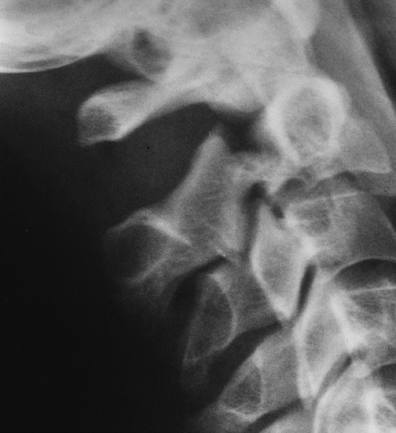

![]() |

FIGURE 3-22 Flexion distraction injury with posterior ligament tear at C5–C6. Flexion (A) and extension (B)

views show subluxation and widening of the interspinous distance and facet joints with flexion that reduces with extension. Treatment-posterior fusion. |